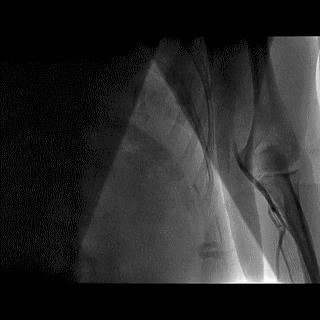

高位桡动脉是前臂动脉分支异常中最常见的类型,发生率大约为2.4%~8.3%,多半存在高位桡动脉的患者中约2/3起源于肱动脉,通常对于起源于肱动脉水平的高位桡动脉患者TRI的治疗成功率相对较高。另约1/3患者的桡动脉起源于腋动脉,又分为三种常见的类型(图3):

图3 桡动脉起源于腋动脉的三种常见类型

第一类为桡动脉直接从腋动脉发出,与肱动脉、尺动脉间无交通支存在;

高位桡动脉-1型

第二类为桡动脉起源于腋动脉,在肘关节水平与肱动脉和尺动脉间存在有交通支;

高位桡动脉-2型

第三类自腋动脉发出细小桡动脉支,但在肘关节水平有较大的桡-尺吻合支。

高位桡动脉-3型